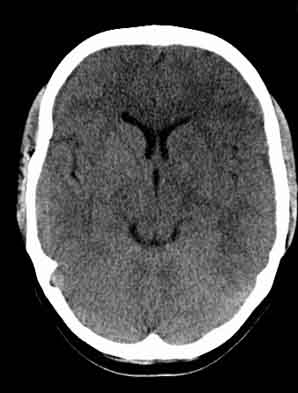

患者,女,29,头痛呕吐2月余,已建议增强或mri进检。

脑沟裂消失,脑白质密度似有减低,考虑脑炎。

左额叶白质密度减低,考虑脑炎,建议增强或mri .

大脑表面脑沟裂消失,颅压高的表现,经常遇到这样的现象,都没有一个明确的结论,望高人指点。

双侧脑室前角、旁周围白质低密度减低,边界模糊不清,患者女性:大胆推测,脑白质脱髓鞘改变。mri检查